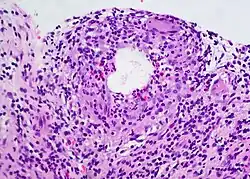

A chalazion (/kəˈleɪziən/; plural chalazia or chalazions) or meibomian cyst[4] is not a cyst but a granuloma[5] in the eyelid that results from a blocked meibomian gland.[6][7] It typically occurs in the middle of the eyelid, red, and not painful.[2] They tend to develop gradually over a few weeks.[2]